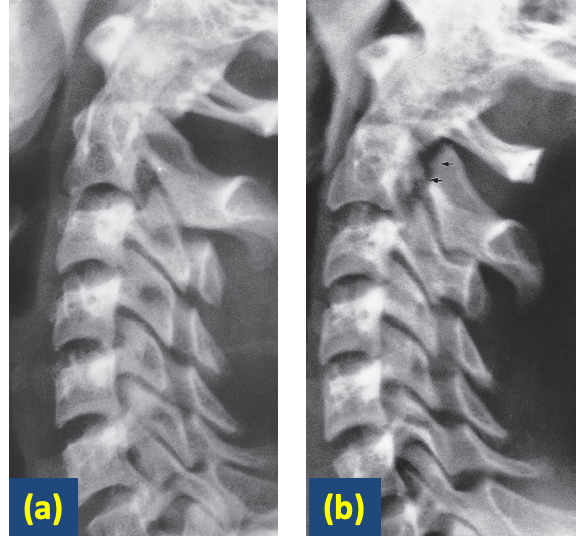

Flexion and extension views. In the cervical spine, injury may cause alteration in the alignment of the posterior borders of the vertebral bodies. This is usually much more obvious on a film taken with the neck flexed

Flexion and extension views demonstrating a fracture.

A) An extension view of the cervical spine does not reveal a fracture.

B) flexion view clearly shows the fracture of the arch of C2.